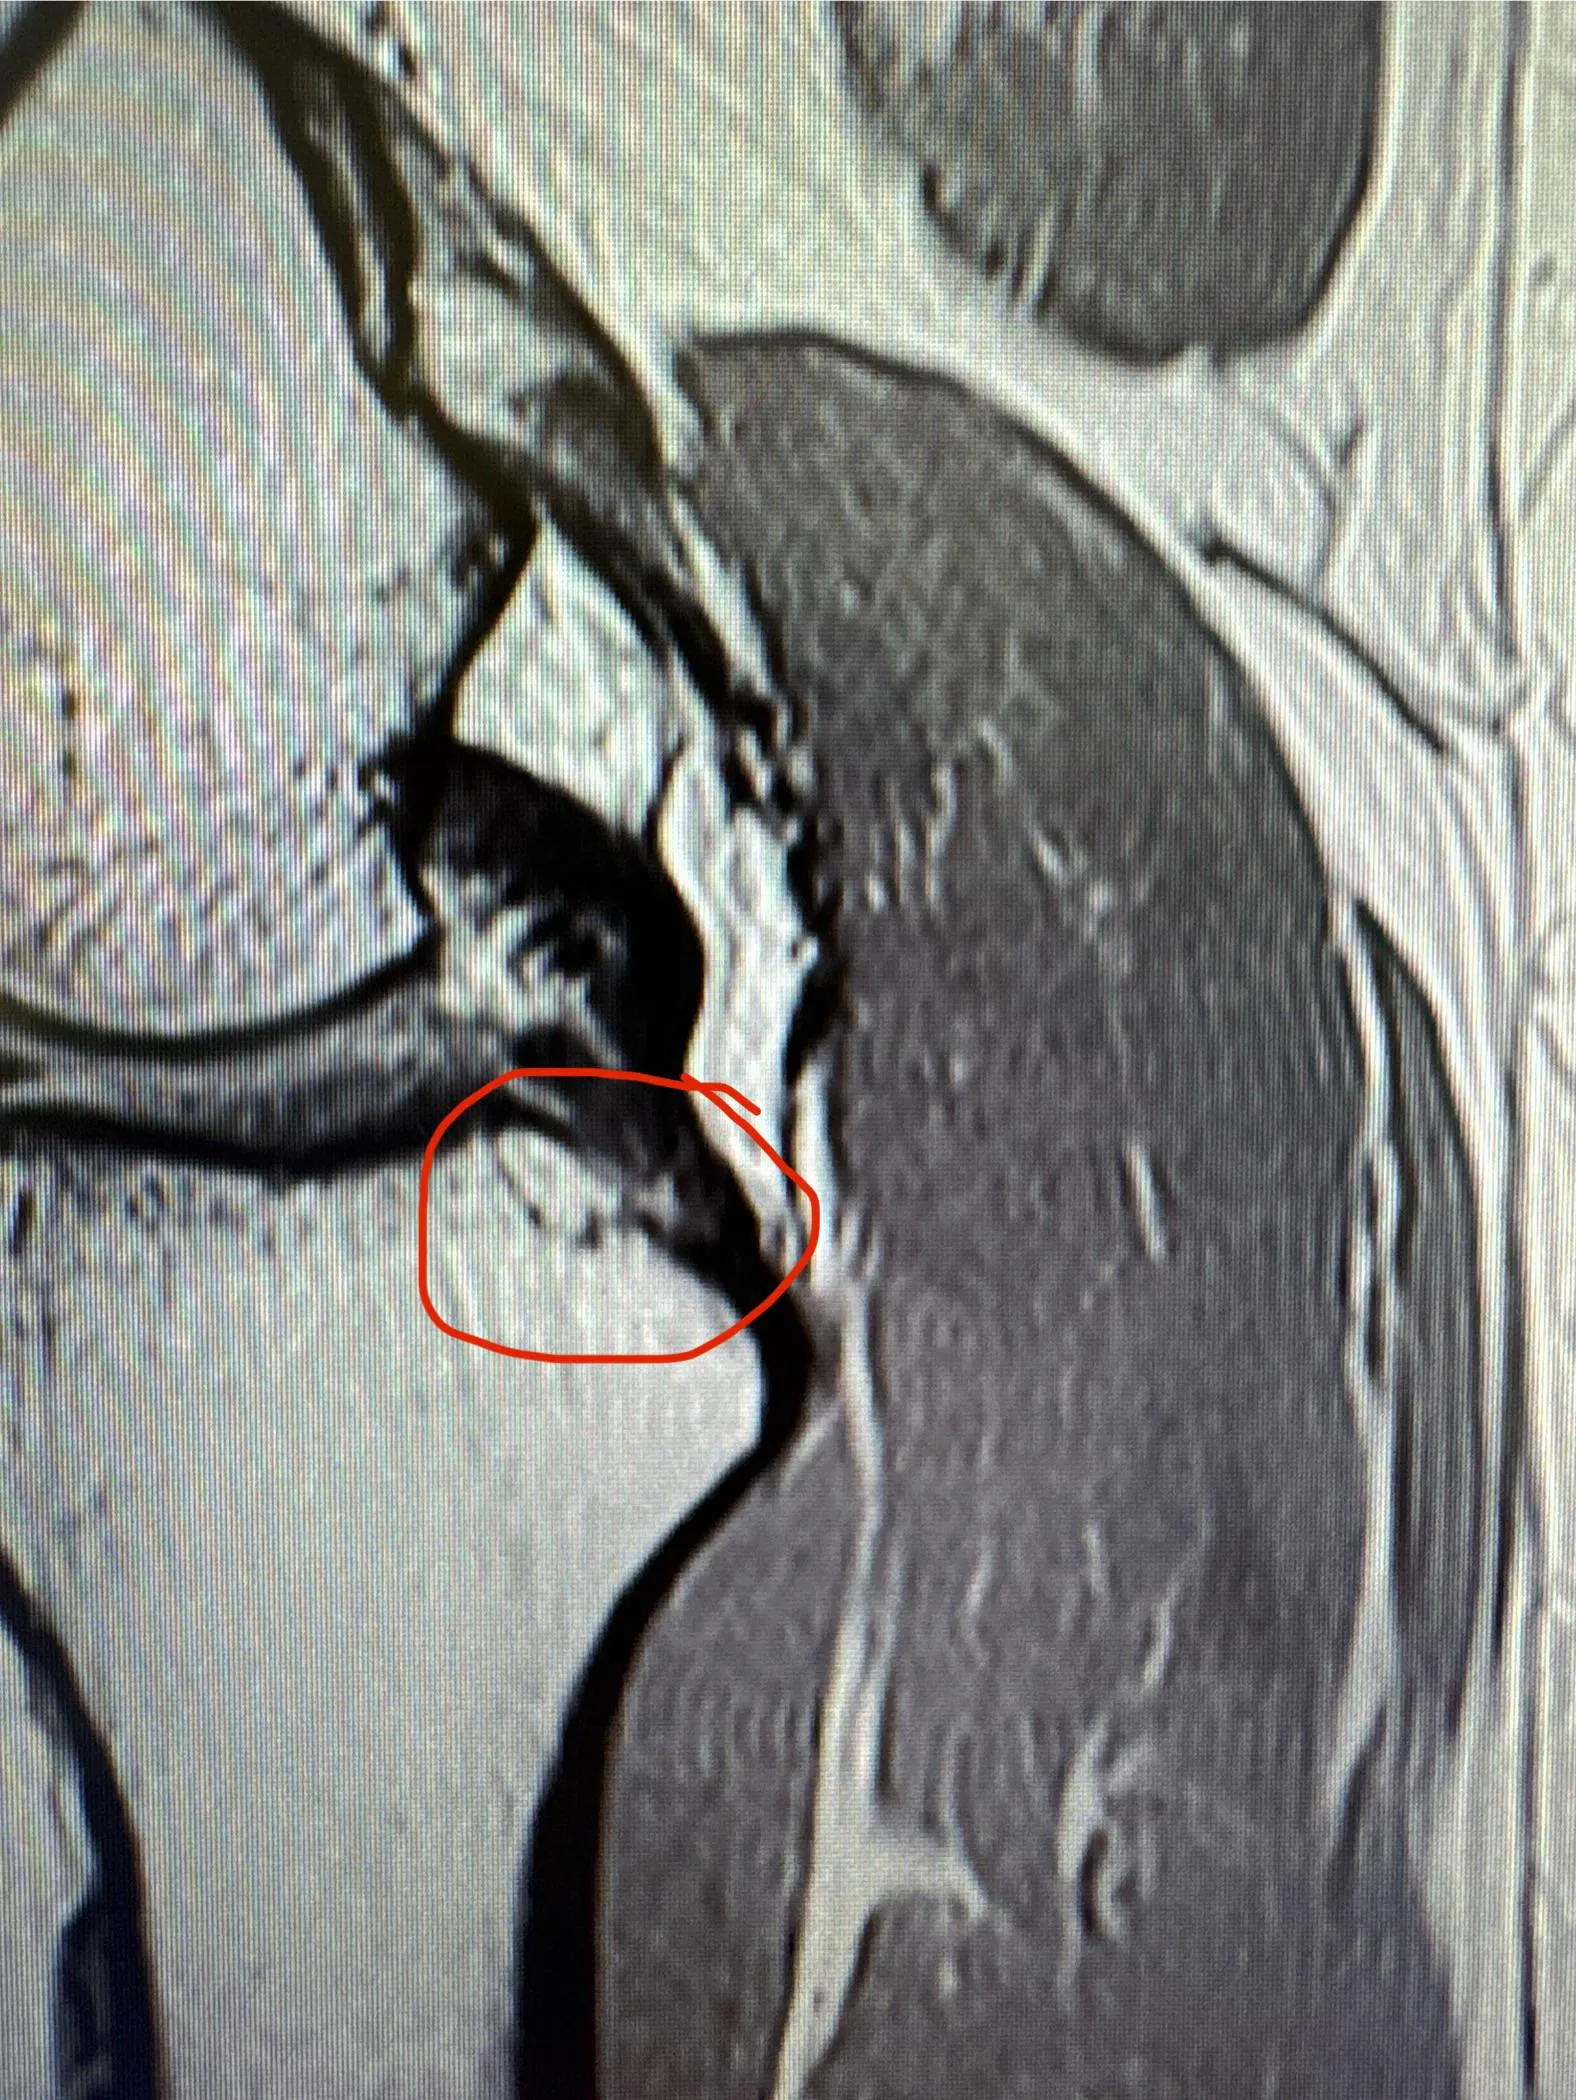

Is this a fracture? nudes

injuries